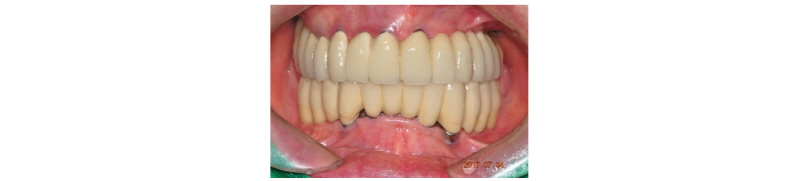

전악 발치 후 하악에는 이공 사이에 6개의 임플란트를 상악에는 8개의 임플란트를 식립하기로 계획하였으나 조기 부하에 의한 임플란트 실패가 우려되어 상악에는 11개의 임플란트를 수술하고 그중 5개의 임플란트를 이용하여 상악 하악 모두 조기 부하를 시도하였다(Fig. 2, 3). 2010년 9월 임플란트 식립과 봉합 후 픽업 임프레션 코핑을 이용해서 인상을 채득하고 상악의 경우 임시치아를 1-piece로 만들었고(Fig. 4) 하악의 경우 구치부의 캔틸레버가 길어서 레진으로 만드는 임시치아는 힘을 버틸 수 없으므로 바로 기성 어버트먼트에 PFM을 1-piece로 제작하여 술 후 2주 후에 부착했다(Fig. 5). 25, 26, 27은 상악동 거상술과 동시에 픽스쳐를 식립하고 묻어두었다. 5개월 뒤 25, 26, 27번 임플란트의 2차 수술을 시행하였고, 처음의 우려와 상관 없이 조기 부하에 사용했던 5개의 임플란트는 모두 골유착에 성공하였다. 단 하악 좌측 견치 부위의 임플란트가 조기 부하의 영향으로 골유착이 양호하지 않은 것으로 보였으나 환자는 불편감이 전혀 없었고 하악의 보철이 1-piece로 제작되어 있었기 때문에 환자에게 고지 후 그대로 유지하기로 하였다. 상악 좌측 구치부의 2차 수술 후 2개월을 더 치유시킨 후 수술한 지 7개월 만에 2011년 4월 상악 최종 보철을 완성하였다(Fig. 6, 7).

상하악 무치악 환자에서 상악에 11개의 임플란트를 수술 한 후 5개의 임플란트를 사용하여 고정성 임시보철물을 만들고 즉시 부하를 가하였으며 하악에서는 6개의 임플란트를 양쪽 이공 사이에 식립하고 제 1 대구치까지 연장되는 캔틸레버 보철물을 만들어 즉시 부하를 가했다. 치유되는 동안 좌측 최후방에 식립된 임플란트만 골유착에 실패했고 나머지 5개의 임플란트는 정상적으로 치유되었다. 상악의 경우 즉시 부하에 사용되었던 5개의 임플란트를 포함해 11개의 임플란트가 모두 골유착에 성공했다.